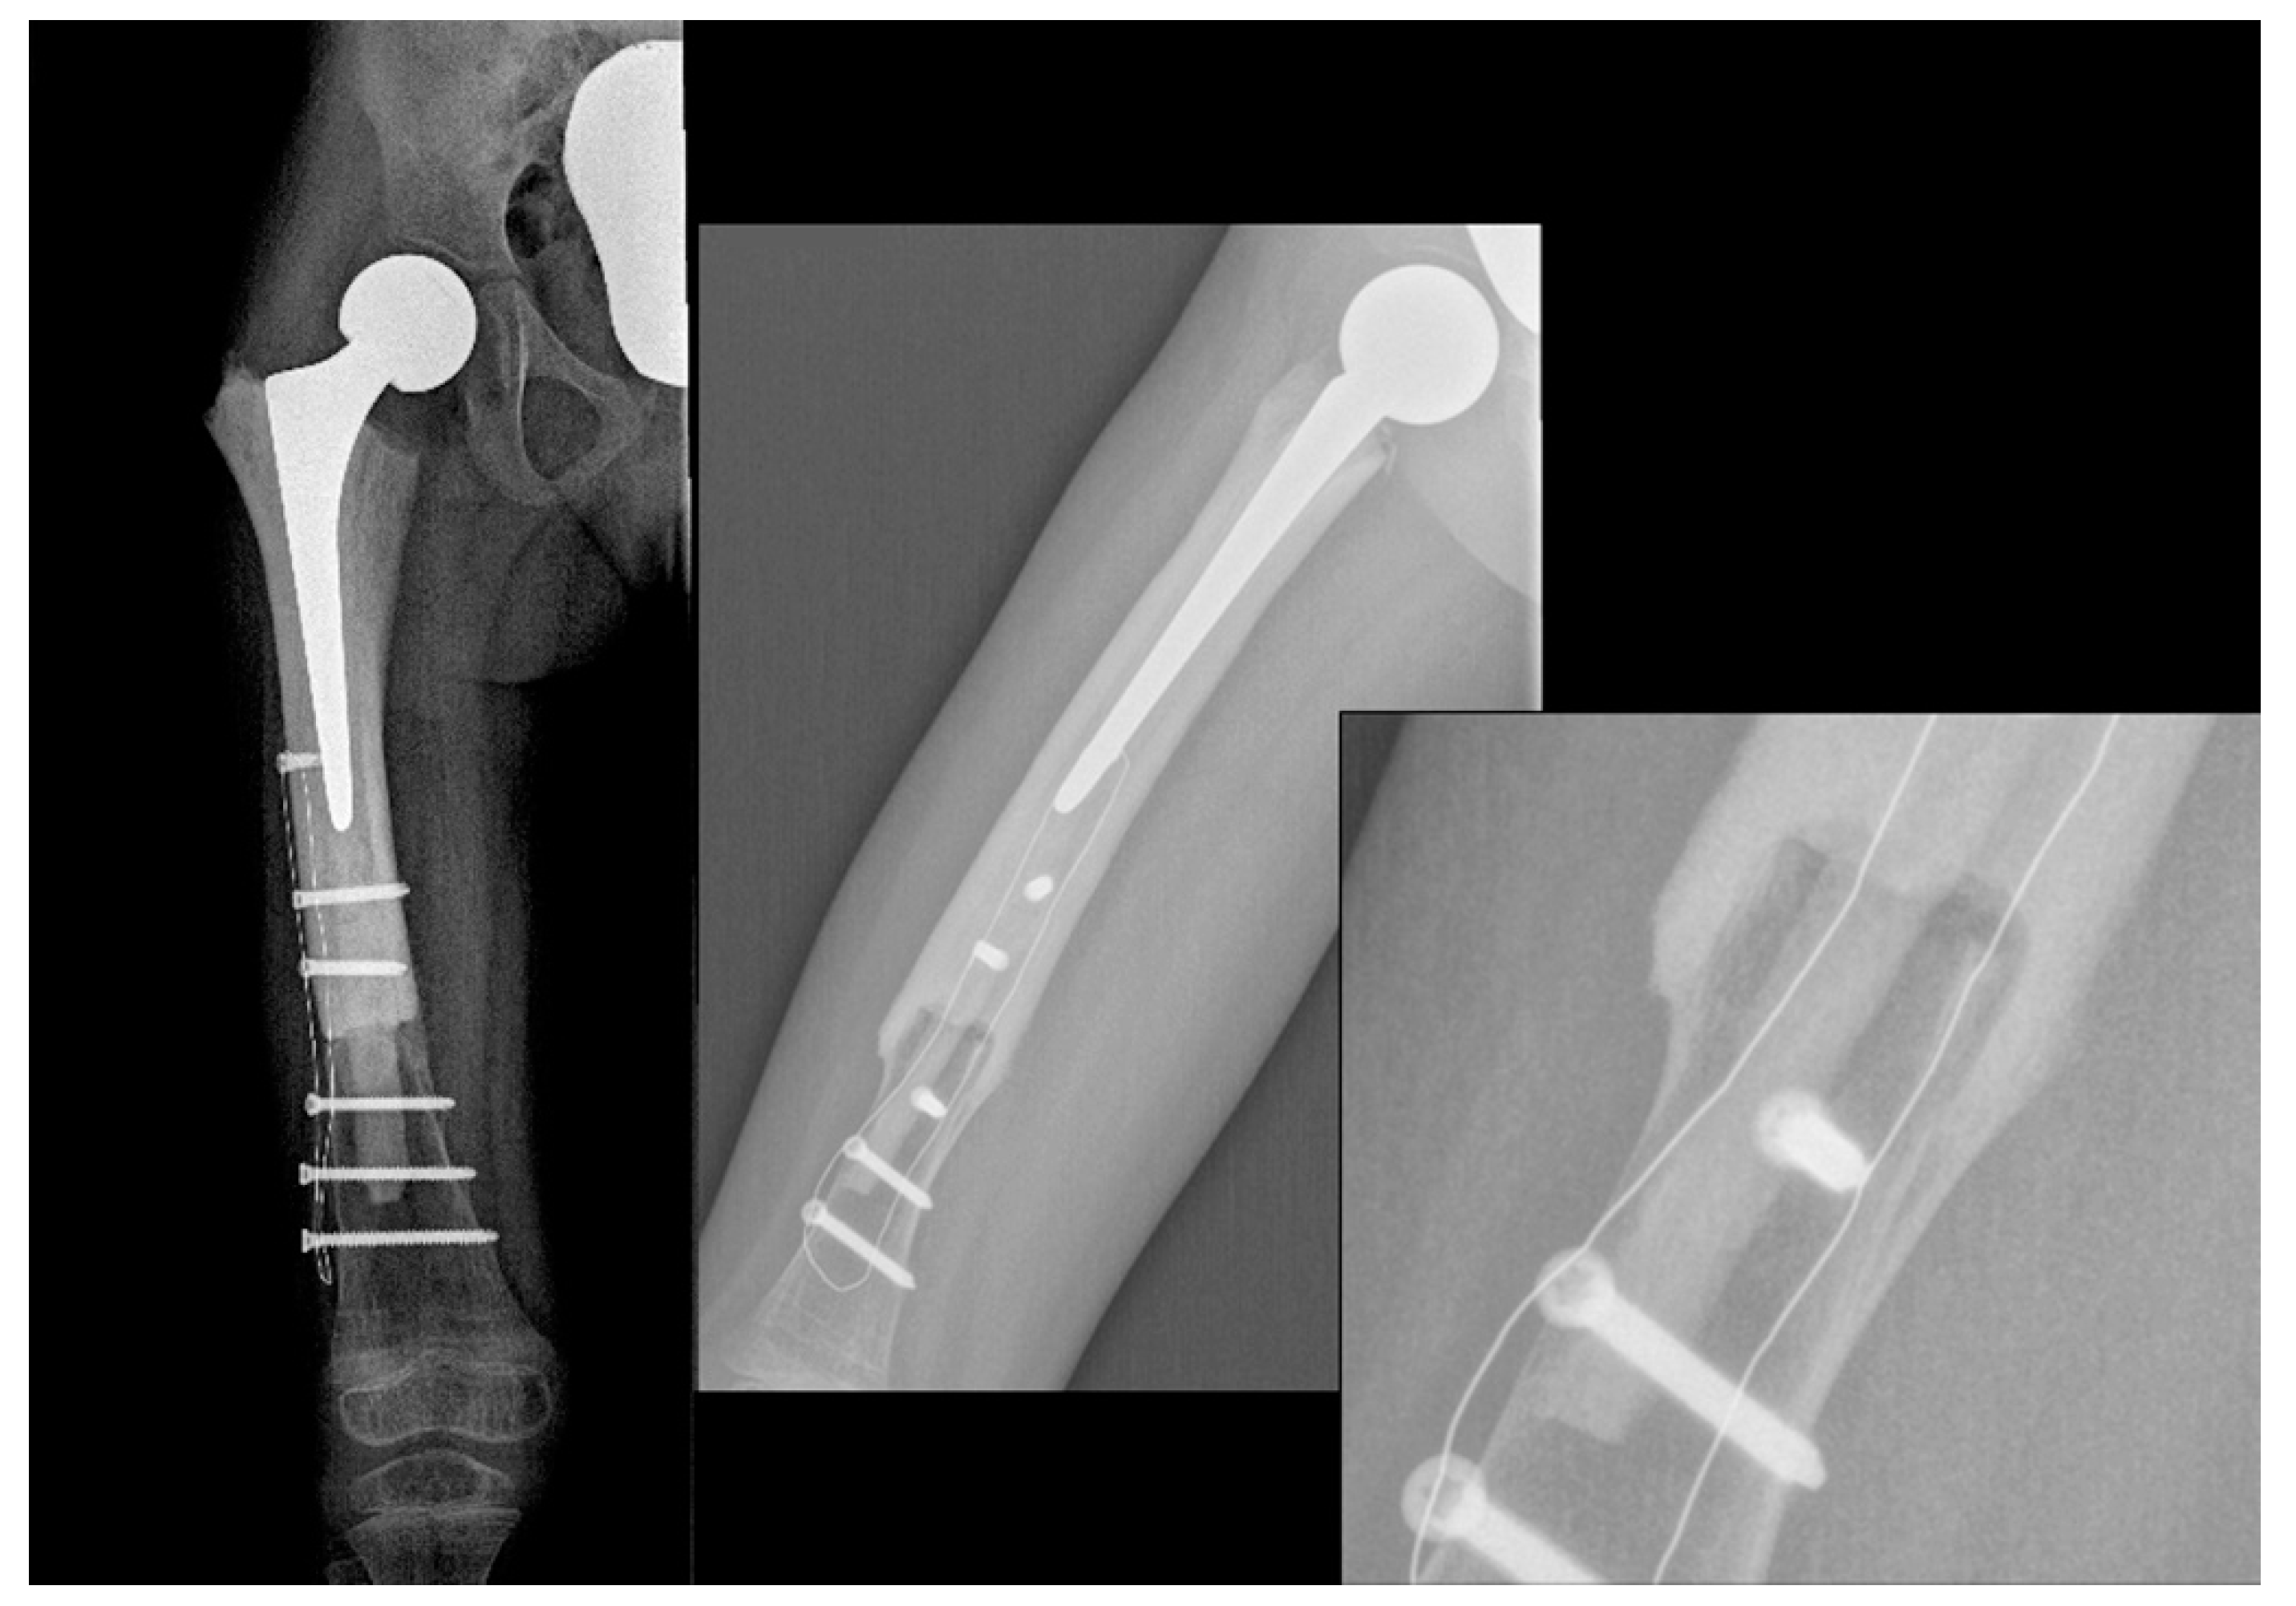

2. Case Report